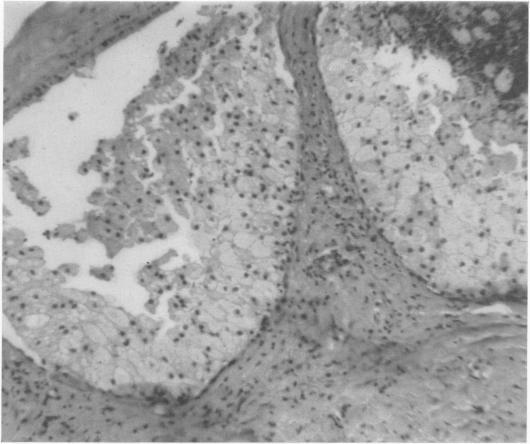

Can breast carcinoma be anticipated? A follow-up of benign breast biopsies.

Ann Surg. 1968 Jun;167(6):829-38. doi: 10.1097/00000658-196806000-00003.